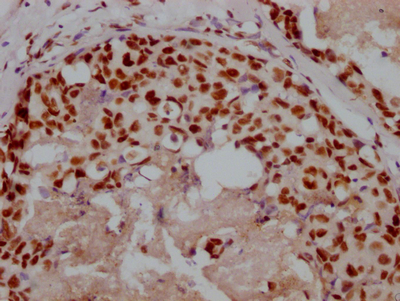

Immunohistochemistry of paraffin-embedded human prostate cancer using CSB-PA138304ESR2HU at dilution of 1:100